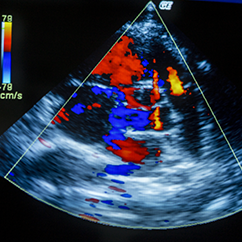

The Cardiovascular Division at LAUMC-RH empowers itself through a solid and rigorous practice, with a variety of scientific activities that have provided our division with permanent exposure to the front-lines of science in cardiovascular disease. Our Catheterization and Interventional Cardiology Unit is one of the pioneering entities within Lebanon that served as a pilot center for the establishment of the Lebanese Interventional Coronary Registry (LICOR). Our division is a highly recognized and esteemed institution within regional, European and Lebanese-American medical circles. It has established close connections with many countries such as France, Italy, Monaco, Germany, Poland, Serbia, Greece, Belgium, Egypt, Saudi-Arabia, Kuwait, Bahrain, UAE, Iraq, and Jordan. Clinical Units & Services: A team of cardiologists, interventional cardiologists, cardiovascular medicine specialists, clinical pharmacist, fellows & residents are running the activity in the division. Our mission is to provide the best treatment and therapeutic approach for our patients. Our path to excellence is founded upon principles of mutual respect and capacity building, all within a team-driven atmosphere. As an affiliate of the Lebanese American University, we continuously invest in our knowledge, and transmit expertise and research into the generations to come. We are solid and rigorous in our practices where the application of evidence-based medicine is reinforced within a congenial environment for our patients. Our vision is to fully nurture and establish leadership status within the Lebanese cardiology community as pioneers within the field with strong readership among prominent academia and medical specialists.